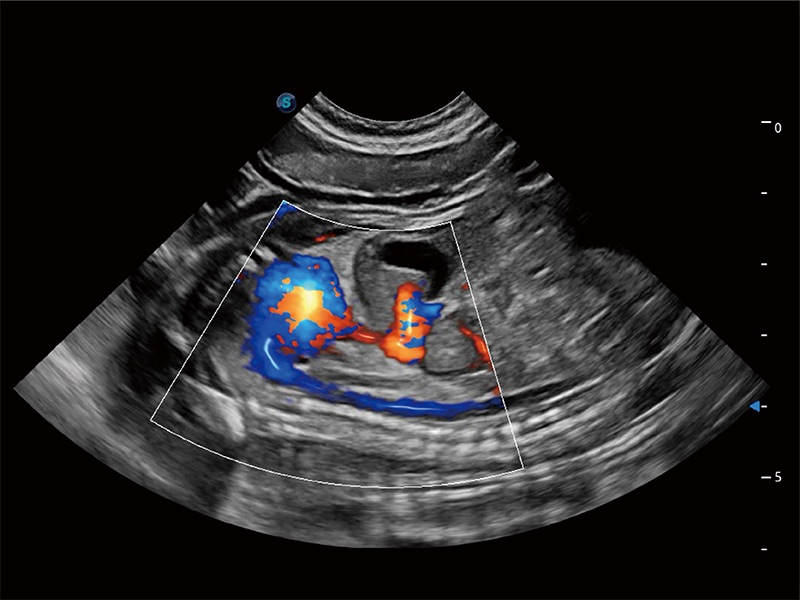

优异的基础图像

ProPet 80 全新的动物超声智能软件和丰富的探头群,为动物医生提供了高清晰度和精细分辨率的图像,无论在宠物、马科、畜牧还是实验室动物等应用中都可以轻松应对,为您的日常工作带来满意的体验。

(犬)胎儿主动脉弓立体血流

(犬)二腔心血流